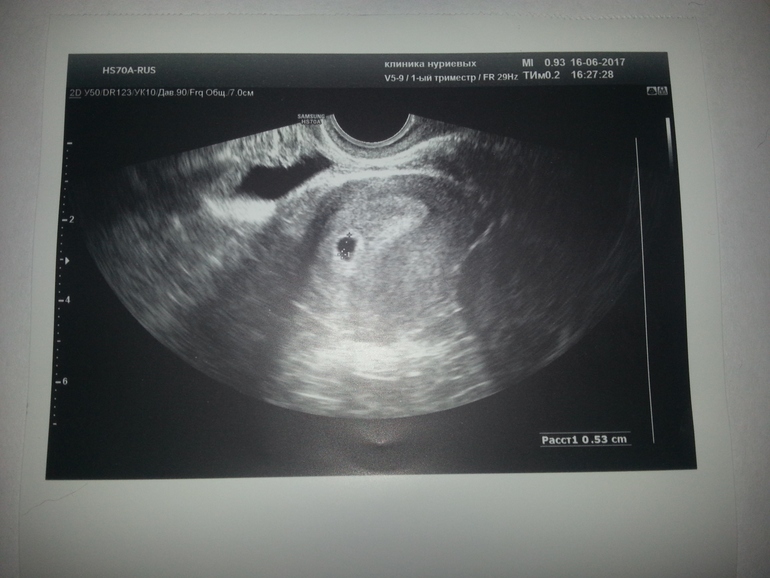

Нас нашли!!!

Урра!нас тоже нашли!толькл фото мне не дали (

Классно так!!!!!! А Вы сколько мм и какой срок поставили?

3.5мм.Но срок 2-3 недели .вам прям до дня так точно написали )